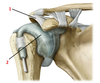

1? 2?

1: Sternoclavicular joint

2: Articular disk

3?

Costoclavicular ligament

1? 2?

1: Acromio-clavicular ligament

2: Coraco-clavicular ligament

1? 3?

1: Labrum

3: Glenoid cavity

2?

Glenohumeral capsule

1? 2?

1: Coraco-acromial ligament

2: Subacromial bursa